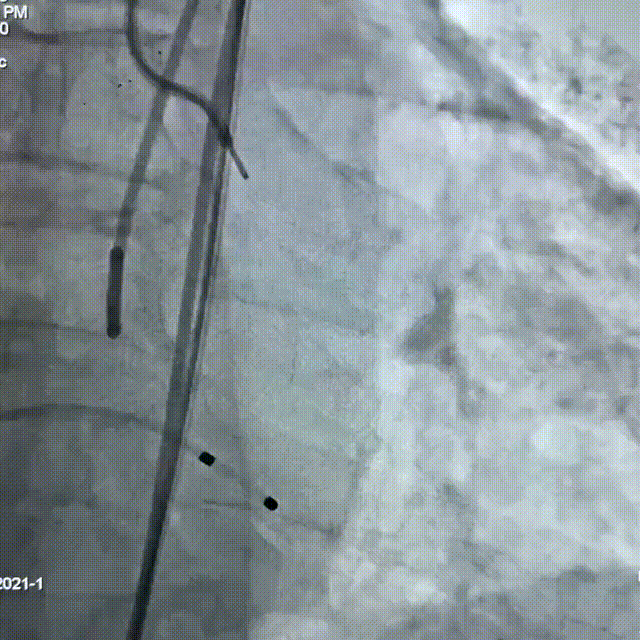

交换超硬导丝至左心室,经右股动脉送入预装有Myval™ 26mm瓣膜的输送系统,成功完成跨瓣操作到达主动脉根部,调整释放深度;

参考术前CT测量值,调整瓣膜至释放前最佳高度,缓慢释放近1/3长度时复查主动脉根部造影,确认瓣膜高度适合,临时起搏180次/分,以80:20比例23±1mL快速释放瓣膜至瓣膜工作区完全打开,于标准位置释放瓣膜;

复查造影提示瓣膜固定良好,形态尚可,未见明显反流;复查超声提示瓣膜功能正常,平均跨瓣压差下降至5.01mmHg,未见明显瓣周漏;最后退出鞘管,缝合血管。